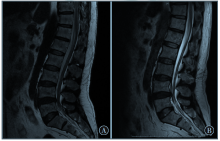

髓系肉瘤是一种髓系不成熟细胞在髓外组织浸润形成的实体恶性肿瘤,可合并存在第二种血液学疾病,临床症状缺乏特异性,具有较高的误诊率,现报道1例髓系肉瘤合并嗜酸性粒细胞增多症、多发性骨髓瘤的患者,并复习相关文献,以提高对该病的认识。